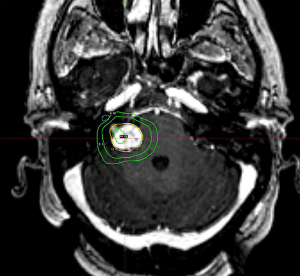

Typical management options include observation, surgical excision, SRS, or endovascular embolization. The goal of treatment is complete obliteration of the vascular nidus to eliminate the risk of hemorrhage. Observation may be appropriate for large volume AVMs (4–5 cm diameter) in patients without prior bleeding and whose AVMs lack other high-risk features (66). SRS is considered for patients with unresectable AVMs, with the best outcomes for small volume AVMs or otherwise located in non-critical locations where single doses >18 Gy to the AVM margin are feasible. There is a protracted response time following SRS with the earliest obliterations noted within 2–3 months, approximately 50% after one year and up to 90% within 3 years. If, at the end of three years there is still residual AVM, repeat SRS or another management strategy may be considered. A threshold of radiation dose is required to achieve AVM obliteration, with >80% obliteration rates above 18 Gy, and the chance of cure based upon volume and location (70). The side effects of SRS for AVMs will also differ based upon location in the brain. For AVMs with treatment volumes expected to be larger than 15 cc, it is recommended to perform volume-staged or dose-staged SRS as increased rates of complications or lower rates of obliteration efficacy are reported at these higher volumes (71-75). An example of Gamma Knife SRS treatment for a small non-resectable AVM of the left tectum is illustrated in Figure 4.